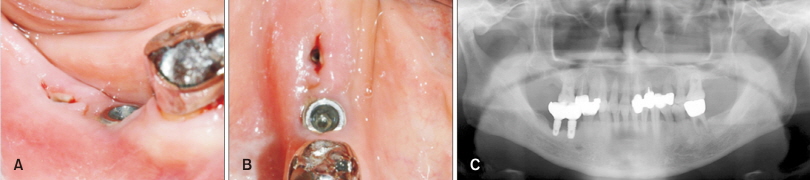

54세 남자 환자가 #46번, #47번 부위에 식립된 임플란트의 불편감을 주소로 내원하였다. #47번 임플란트는 전장의 2/3, #46번 임플란트는 전장의 1/2을 넘어서는 골소실을 보였으며 각화치은의 심한 소실이 관찰되었다(Fig. 4). 임플란트 제거를 계획하였으며, 환자는 임플란트 제거 후 이 부위를 다시 임플란트로 수복하기를 원하였다. 이미 심한 골파괴가 있었기 때문에 골소실이 추가로 진행된다면 임플란트 식립이 어려워질 것이 예상되어, 임플란트 제거와 동시에 치조제 보존술을 계획하였다.

Fig. 4. Clinical and radiologic findings at an initial visit of the patient 1. Clinical photograph at a facial view (A), clinical photograph at an occlusal view (B), panoramic view (C).